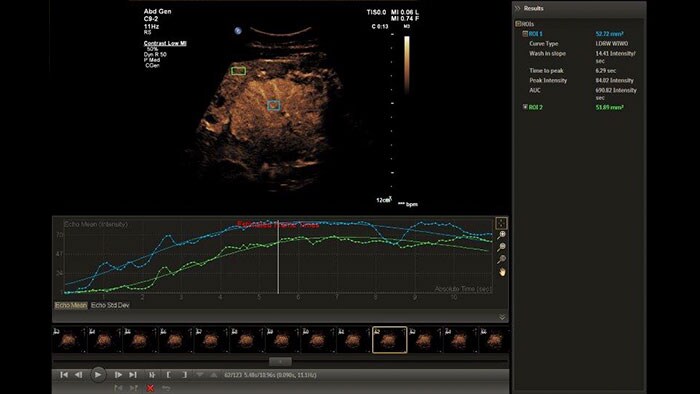

Perform advanced analysis of 2D, Color and CEUS data

The Q-App Region of Interest (ROI) provides dedicated tools for spatial and temporal analysis of regions of interest in 2D, color and contrast enhanced* ultrasound exams (CEUS). This Q-App also provides basic 2D measurement tools (distance, area) as well. For CEUS applications, multiple motion compensated regions can be defined for contrast bubble analysis to generate wash-in/wash-out curves for lesion blood flow assessment.

Benefits

*Ultrasound contrast agents are approved for use in Left Ventricular Opacification (LVO), focal Liver lesions characterization, and for the evaluation of suspected or known vesicoureteral reflux in pediatric patients’ urinary tract ultrasonography.